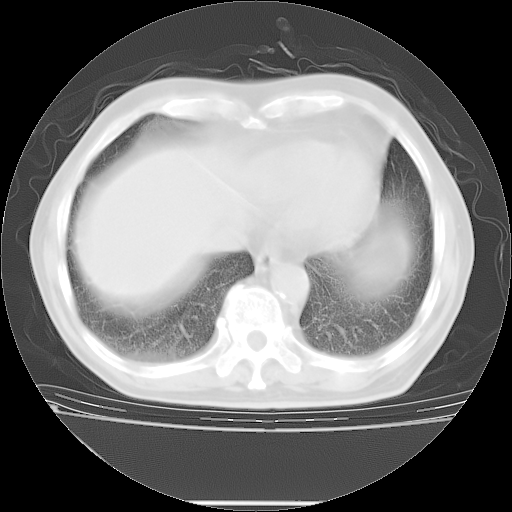

今天复查肺部CT,发现双肺广泛磨玻璃样改变。所以我把3月19日和5月9日相隔50天的肺部CT上传。请大家会诊。

5月9日肺部CT(在4月27日齐鲁医院肺部CT描述部分肺组织磨玻璃样改变,12天后肺组织广泛磨玻璃样改变)

2009年5月9日肺部CT